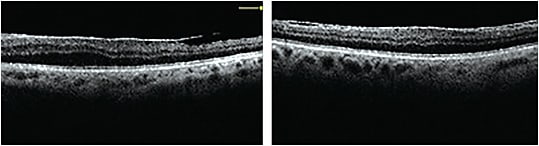

Aniseikonia may also occur when posterior ocular damage causes axial elongation from compression or stretching of the retina or macula (Okamoto et al, 2017). For example, scleral buckle surgery or an epiretinal membrane (Figure 1) may cause symptomatic retinal aniseikonia. Interestingly, unilateral functional vision deprivation (such as congenital ptosis) or cataract in children causes axial elongation, thus also leading to aniseikonia (Zhu et al, 2019).